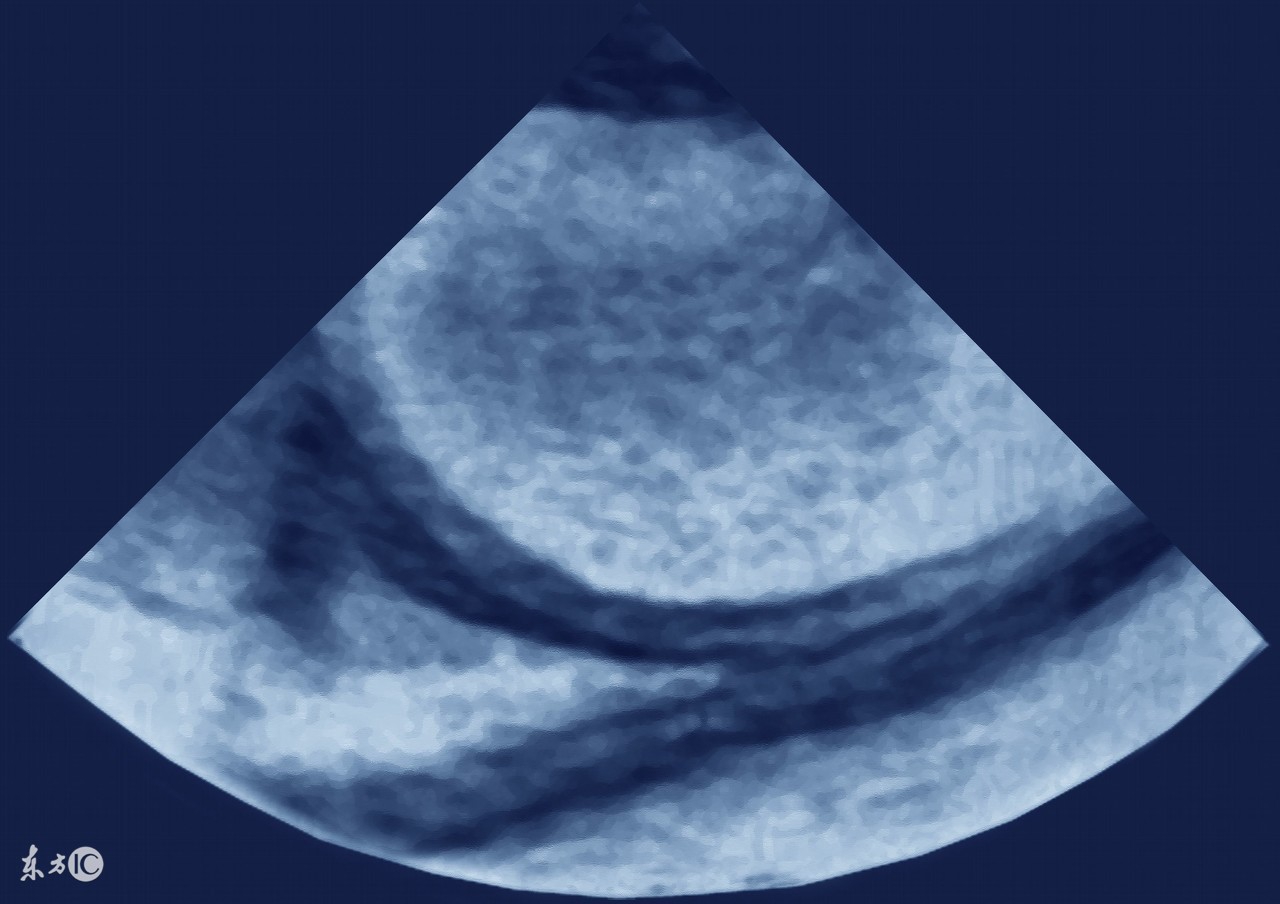

借此机会,就来和大家说一说哪些癌症会引起腹水,因为有不少病人是因为发现肚子鼓鼓的,做B超一看,肚子里有水(腹水),于是找原因,是什么原因引起的腹水?

要诊断是癌性腹水,当然必然要找到证据,那就是在腹水里找到癌细胞,但有时可能不容易找到,我们可以结合临床资料,综合进行判断。